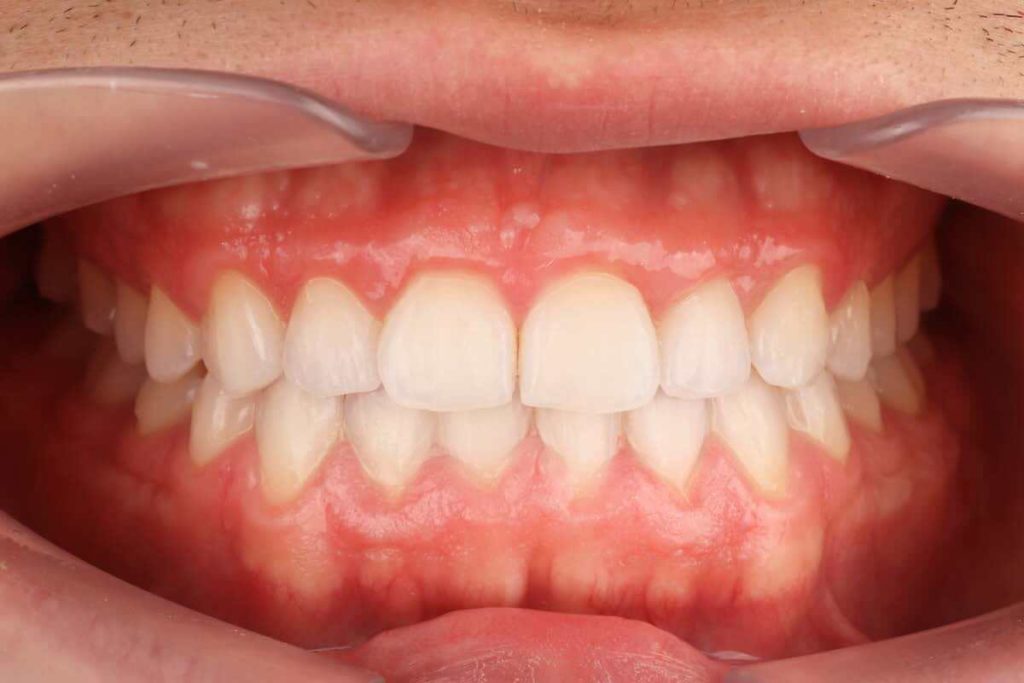

SITUACIÓN FINAL

Se resuelve el apiñamiento, la relación entre los caninos y los molares de clase I, y se estabilizan el overjet y el overbite. Corrección del desplazamiento de la línea media. En el paso final se realizó un blanqueamiento y restauraciones directas en los dientes 12 y 22 .

Colocamos retención fija en el maxilar inferior y retenciones removibles tanto en superior como en inferior.